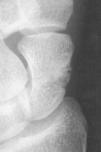

Son aquellas que no varían la forma y el volumen del escafoides, manteniendo su geometría espacial. Son fracturas que aparecen incompletas, precisando tratamiento mínimo y normalmente tienen una consolidación rápida. Este grupo representa sólo el 8% de las fracturas del escafoides14 y comprende los siguientes tipos de fracturas: a) fracturas del tubérculo (Fig. 1), en las que no siempre es necesaria la reducción o inmovilización, y b) fracturas incompletas del cuerpo del escafoides (Fig. 2): el diagnóstico de las mismas puede ser difícil, pudiendo pasar inadvertida. Es importante realizar controles radiológicos periódicos durante el proceso de consolidación para descartar que en realidad se trate de una fractura inestable.

Figura 1. A y B: Fractura del tubérculo del escafoides es una fractura estable que requiere un mínimo tratamiento. Habitualmente la consolidación es rápida.